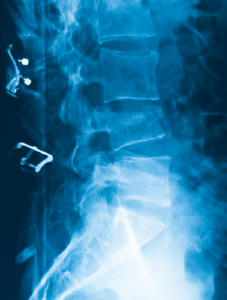

Spinal compression fractures occur when the bone structure becomes so weak and the vertebra virtually collapses on itself, creating a wedge-like shape. This can cause a significant amount of pain and structurally can cause your posture to stoop forward (kyphosis) and chronically can give you the appearance of a hunchback. Both these factors can leave you bedridden and make it difficult for you to take a deep breath making you more susceptible to infections such as pneumonia.

- X-Ray: This is the baseline study you will need to see if you have fracture. Unfortunately, it does not tell us whether your fracture is old or new. In addition, it may be difficult to see small fractures.

If there are any neurological deficits, open surgical treatment may be necessary. This typically involves fusing your spine with hardware. Obviously, this can be very invasive and outcomes can be poor when the bone is weak from osteoporosis.